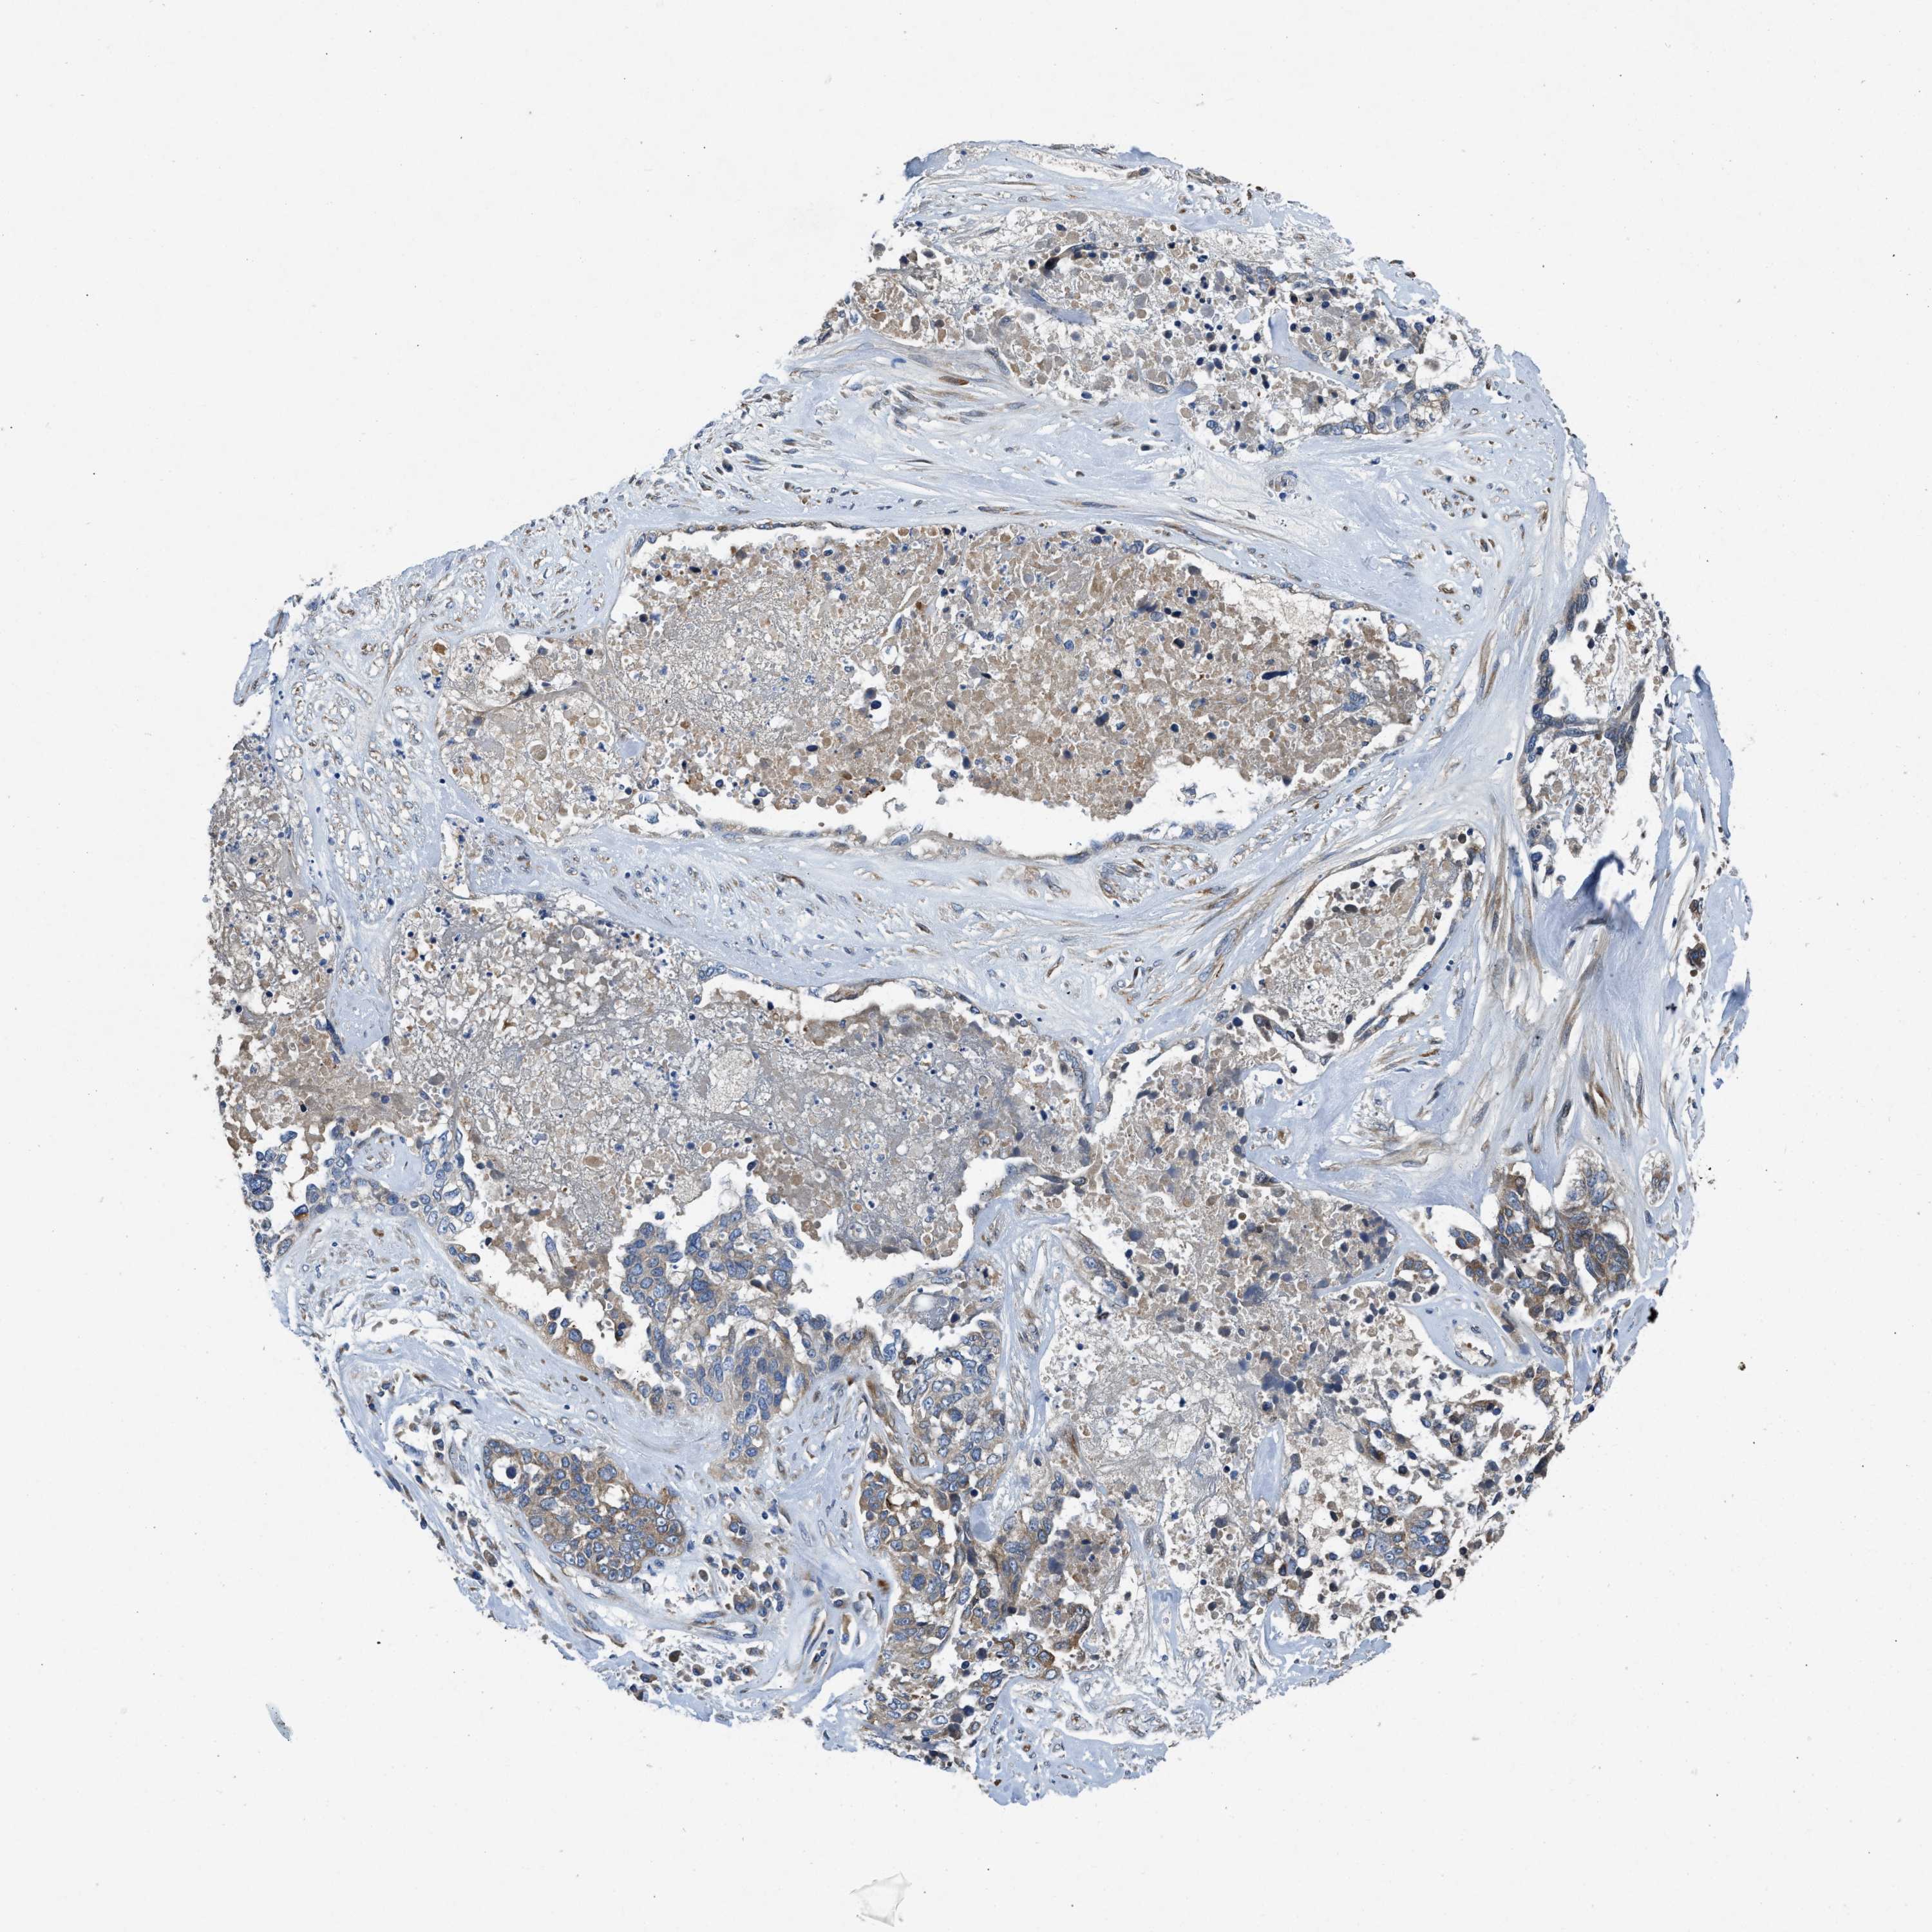

OVARIAN CANCER - Protein expressioni

A mouse-over function shows sample information and annotation data. Click on an image to view it in a full screen mode. Samples can be filtered based on level of antibody staining by selecting one or several of the following categories: high, medium, low and not detected. The assay and annotation is described here.

Note that samples used for immunohistochemistry by the Human Protein Atlas do not correspond to samples in the TCGA dataset.

Antibody stainingi

Antibody staining in the annotated cell types in the current human tissue is reported as not detected, low, medium, or high, based on conventional immunohistochemistry profiling in selected tissues. This score is based on the combination of the staining intensity and fraction of stained cells.

Each image is clickable and will lead to virtual microscopy that enables deeper exploration of all samples and also displays staining intensity scores, fraction scores and subcellular localization as well as patient and tissue information for each sample.

Antibody HPA018284

Staining

High

Medium

Low

Not detected

Intensity

Strong

Moderate

Weak

Negative

Quantity

>75%

75%-25%

<25%

None

Location

Nuclear

Cytoplasmic/membranous

Cytoplasmic/membranous,nuclear

Cystadenocarcinoma, serous, NOS

Carcinoma, endometroid

Cystadenocarcinoma, mucinous, NOS

Carcinoma, NOS